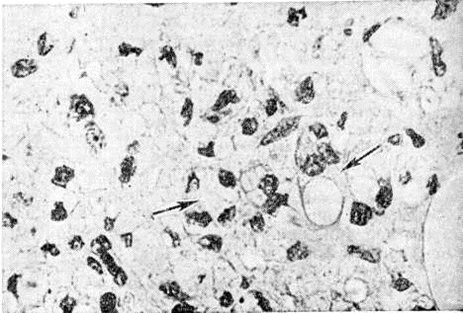

Рис. 8.

Микроскопическая картина кожной гранулемы при туберкулоидном типе лепры: поражение субэпидермальной зоны, инфильтрат состоит из эпителиоидных и лимфоидных клеток, 1 — эпидермис, 2 — субэпидермальная зона, 3 — инфильтрат. Окраска гематоксилин-эозином; × 120.

Рис. 9.

Микроскопическая картина инфильтрата кожи при туберкулоидном типе лепры: стрелками указаны гигантские клетки. Окраска гематоксилин-эозином; × 320.

Рис. 1—6.

Микроскопические картины поражений при различных формах лепры.